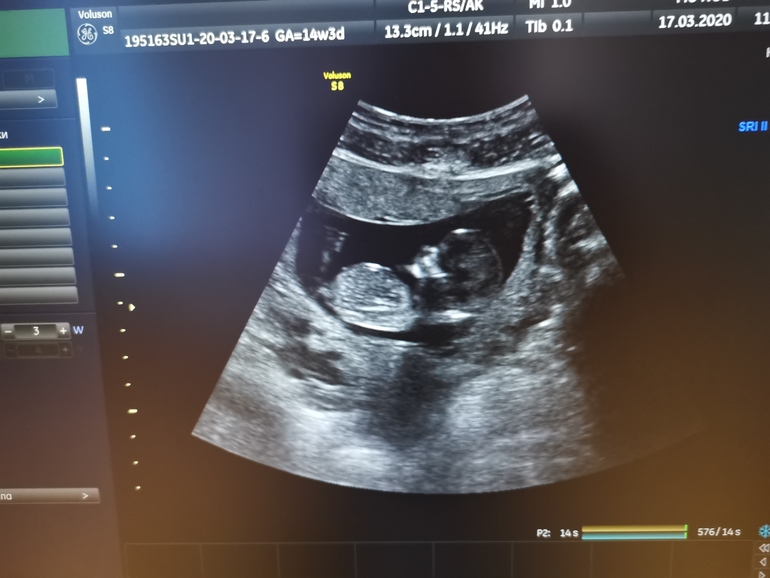

1 скрининг. Пол?

Сегодня наконец-то прошла 1 скрининг. Всё хорошо с малышом, соответствует сроку. Единственное сперва намерили сердцебиение 134, потом ещё раз переделали и было уже 148.🤔 Сей факт будет периодически меня беспокоить до следующего узи. Спросила про половой бугорок, на что мне ответил узист, что ничего не знает про бугорки😂 Не знаю, видно или нет, но может, кто-то увидит по фото? Хочу девчонку, но недавно снился мне сын Аркадий, но так бы я точно не назвала😁